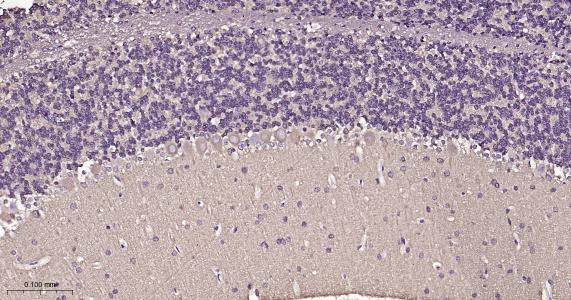

Paraformaldehyde-fixed, paraffin embedded Rat Cerebellum; Antigen retrieval by boiling in sodium citrate buffer (pH6.0) for 15 min; Antibody incubation with beta I Tubulin Monoclonal Antibody, Unconjugated(bsm-33041R) at 1:200 overnight at 4°C, followed by conjugation to the bs-0295G-HRP and DAB (C-0010) staining.

Paraformaldehyde-fixed, paraffin embedded Rat Cerebrum; Antigen retrieval by boiling in sodium citrate buffer (pH6.0) for 15 min; Antibody incubation with beta I Tubulin Monoclonal Antibody, Unconjugated(bsm-33041R) at 1:200 overnight at 4°C, followed by conjugation to the bs-0295G-HRP and DAB (C-0010) staining.

Paraformaldehyde-fixed, paraffin embedded Mouse Cerebrum; Antigen retrieval by boiling in sodium citrate buffer (pH6.0) for 15 min; Antibody incubation with beta I Tubulin Monoclonal Antibody, Unconjugated(bsm-33041R) at 1:200 overnight at 4°C, followed by conjugation to the bs-0295G-HRP and DAB (C-0010) staining.